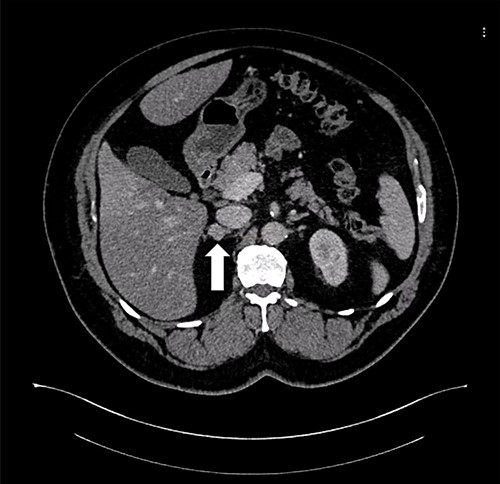

As for the LRA, ports are inserted in similar fashion as the LLA but with more to the right side. An additional port at the right midclavicular line is an optional (Fig. 5). In Patient 1, we started with the LLA to control the blood pressure caused by the adrenal gland and to prevent unnecessary bleeding from occurring. Conversely, we started with LSG in Patient 2 because the priority was controlling his comorbidities by weight reduction. The right hepatic lobe was retracted to expose the subhepatic area. The right hepatic ligaments were released, exposing the inferior vena cava. Dissection lateral to the IVC was continued exposing the right adrenal (Fig. 6). Complete dissection of the adrenal gland was completed and the pedicle was controlled using energy device (Fig. 7). There was constant communication with the anesthesia team during the surgery. After complete dissection of the adrenal gland, it was placed in the endobag and the LSG was conducted similar to the above-mentioned steps (Fig. 8).